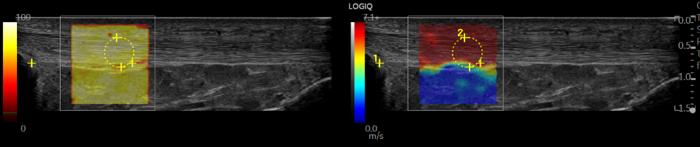

Ultrasound shear wave elastography is an advanced, quantitative method for analyzing functional changes in the patellar tendon, and when used to measure the stiffness of tissue in the patellar tendon, the method has the potential to identify risk factors or indicators of tendinopathy onset. To date, this will be the first time the method is used in a research study on elite professional basketball players.

GE HealthCare’s LOGIQ TM E10s Ultrasound with ML4-20-D transducer was used to perform serial Ultrasound elastography diagnostics on the knee (patellar tendon) of participating players. The ML4-20-D probe uses XDclear TM transducer technology—an innovative combination of advanced materials and acoustic design— that provides high quality images to support musculoskeletal assessment. The LOGIQ E10 Series, equipped with advanced tools including 2D Shear Wave Elastography, enables qualitative and quantitative assessment of tissue elasticity.